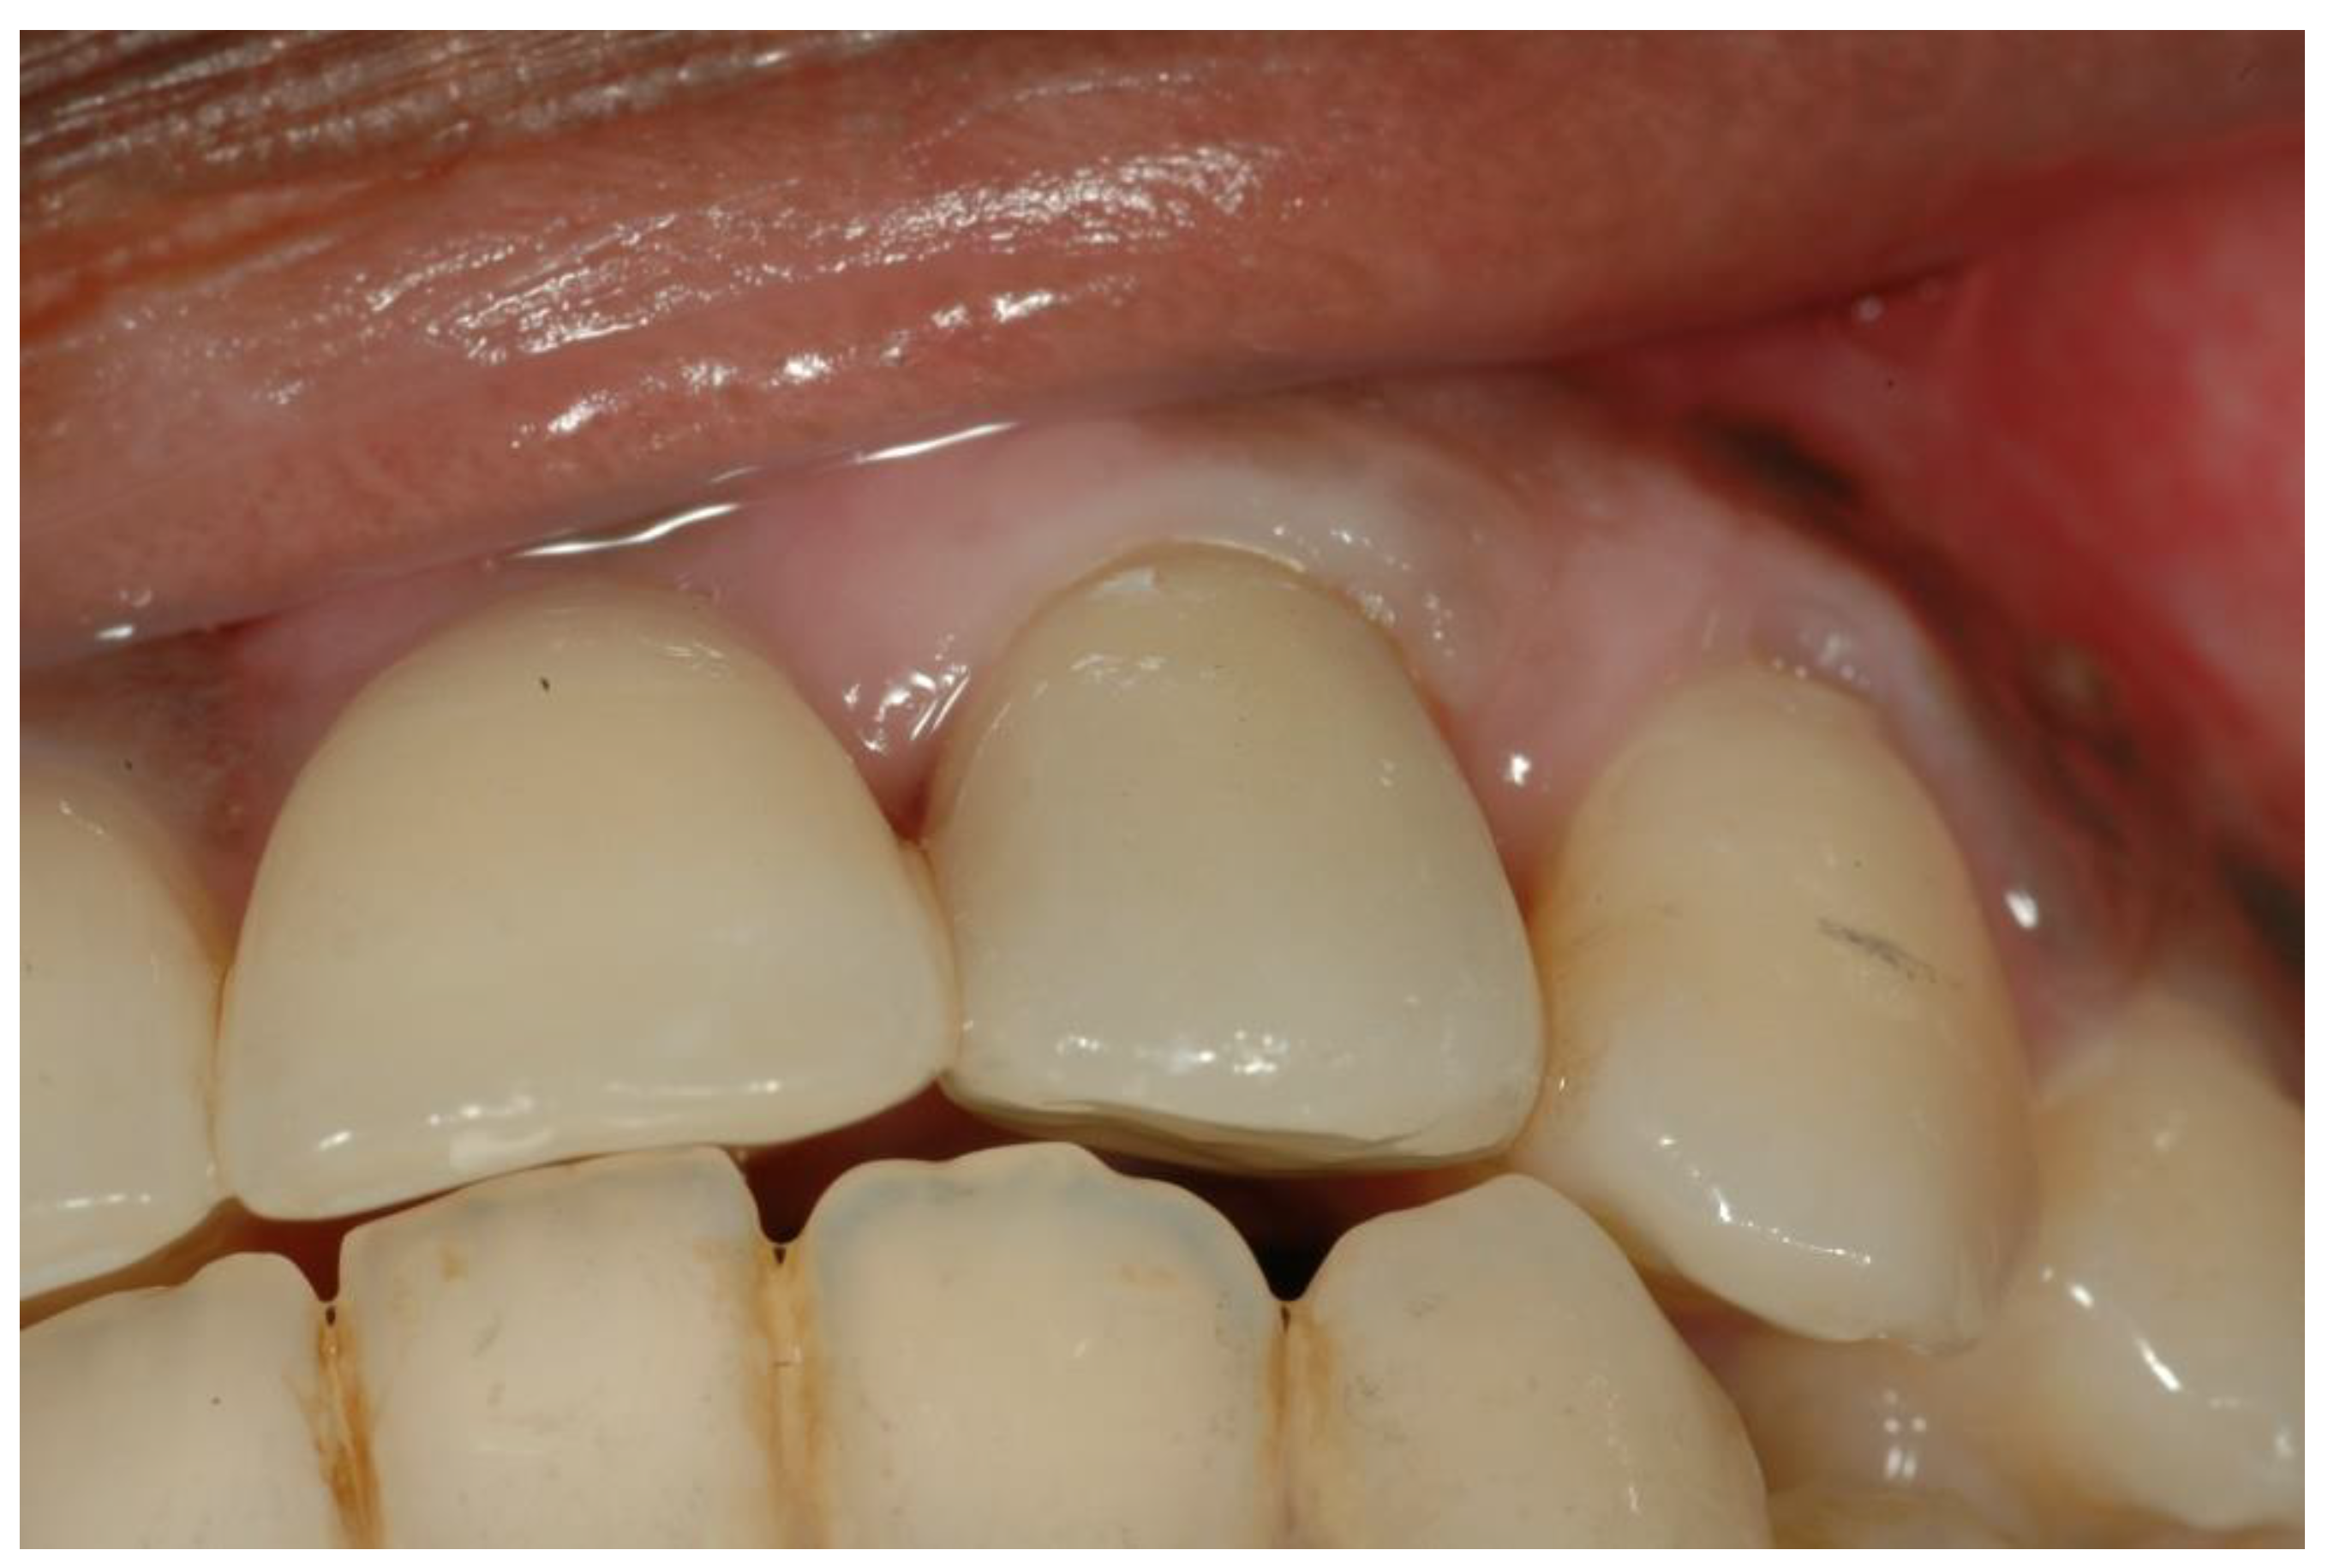

- Six months later, implant insertion followed immediately by a temporary restoration placement.

- Similar permanent ISP metal-free porcelain crown type performed in the same laboratory.